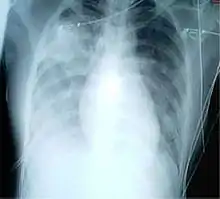

For a case to be considered probable, a chest X-ray must be indicative for atypical pneumonia or acute respiratory distress syndrome.

The WHO has added the category of "laboratory confirmed SARS" which means patients who would otherwise be considered "probable" and have tested positive for SARS based on one of the approved tests (ELISA, immunofluorescence or PCR) but whose chest X-ray findings do not show SARS-CoV infection (e.g. ground glass opacities, patchy consolidations unilateral).[10][11]

The appearance of SARS-CoV in chest X-rays is not always uniform but generally appears as an abnormality with patchy infiltrates.[12]